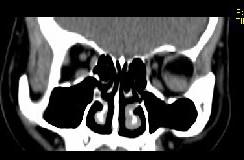

问题 女,52岁,左眼球突出二十余年, T3、T4均正常,影像检查如图所示,应诊断为 ( )

选项 A、血管瘤 B、炎性假瘤 C、脂肪瘤 D、畸胎瘤 E、错构瘤

答案 E